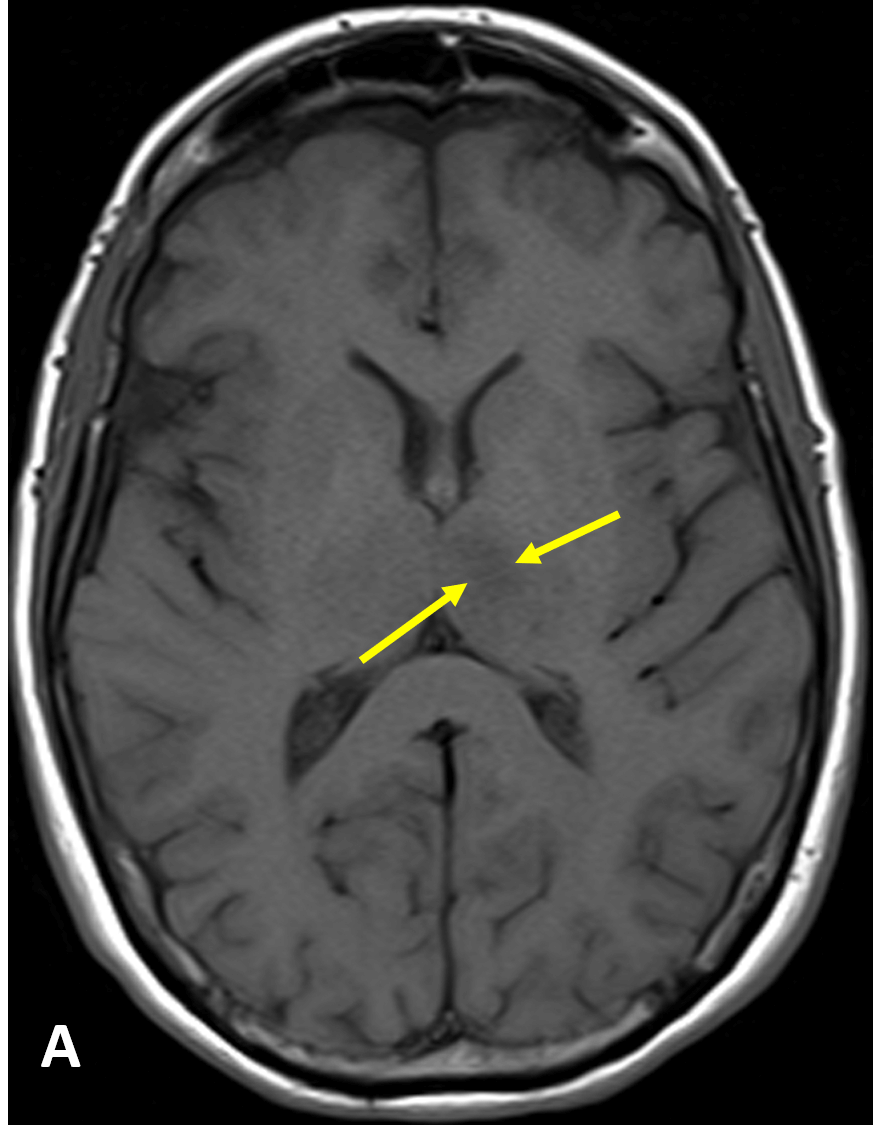

https://adsense.google.com/adsense/u/1/pub-9161951367286286/myads/sites/preview?url=notion6988.tistory.com ⏱️ 경미한 뇌경색이라도 빨리 병원 가야… 42시간 넘으면 약물치료 효과 없어